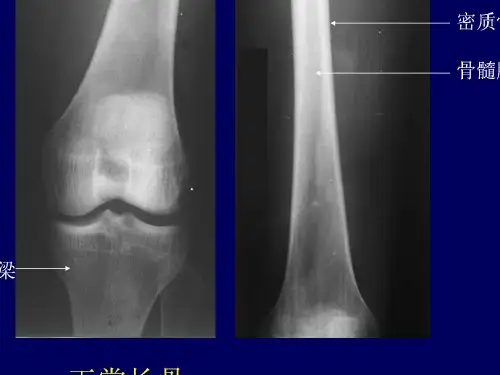

与儿童相比,外形相似,骺与 干融合,骺板消失。两侧形成骨 端,两端有关节面,关节面被覆 透X线的关节软骨。